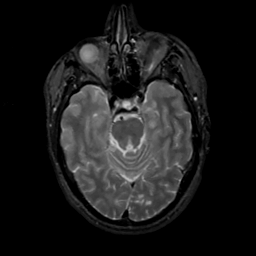

MR Study #10, April 28, 1991 -- Slice #17